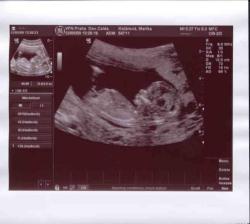

9.4.2009 - kontrola u

apolináře - v dutince se objevil jeden živý plod,

kterému krásně tluče srdíčko

22.5.2009 - NT screening v 1. trimestru

(tatínek poprvé viděl našeho broučka) - u

všeho testovaného dopadlo vše výborně